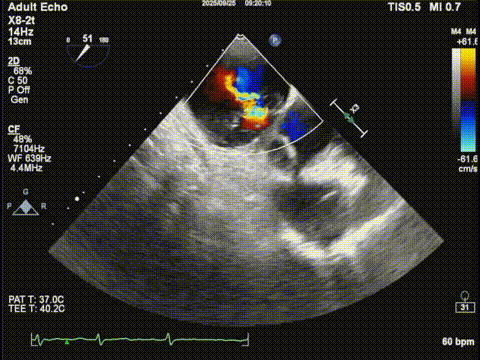

三尖瓣

三尖瓣反流以膈叶脱垂为主,反流主要集中在前叶和膈叶间,从中心区向边缘区的蔓延。后叶又有分了两个叶,分型上属于IIIb型的三尖瓣反流。

三尖瓣膈叶前叶

三尖瓣膈叶前叶color